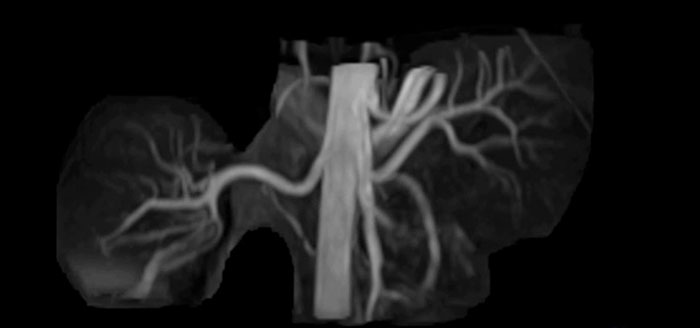

MR-Untersuchung mit Prodiva 1.5T, 72-jährige Patientin mit malignem Melanom am Knöchel. mDIXON TSE bietet eine hervorragende Fettsuppression ohne Verzerrung, wie sie ansonsten bei diesen Extremitäten häufig auftritt.